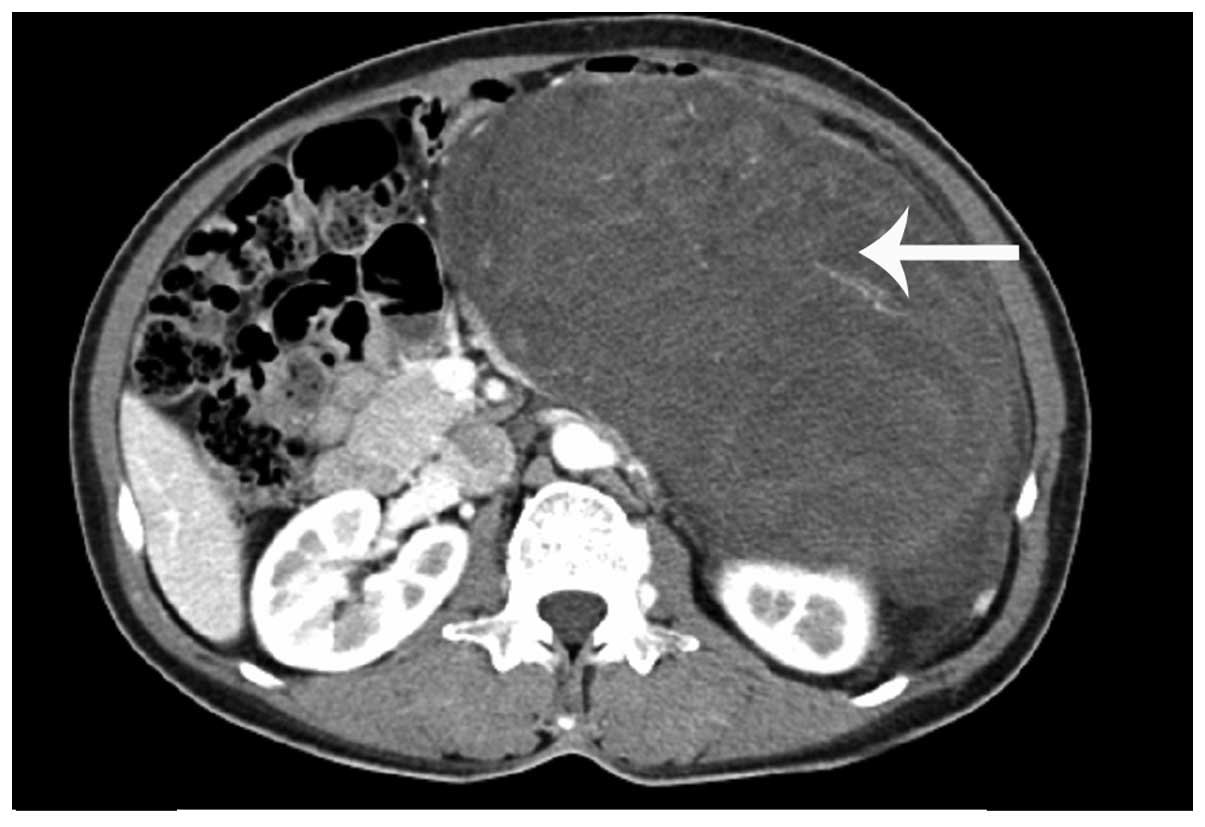

ct leiomyosarcoma retroperitoneal ctisus mr body diagnosis studies case

leiomyosarcoma retroperitoneal radiopaedia

leiomyosarcoma retroperitoneal pathology radiologic archives rg